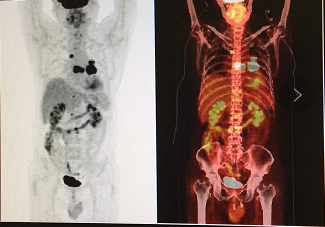

图2 患者进食后和空腹PET/CT图像比较(北京医院核医学科李旭供图)

如图2,这是同一个患者,左边是进食以后做的显像,是不是肌肉摄取特别明显?右边是两天以后空腹重做的检查,图像质量就好多了。